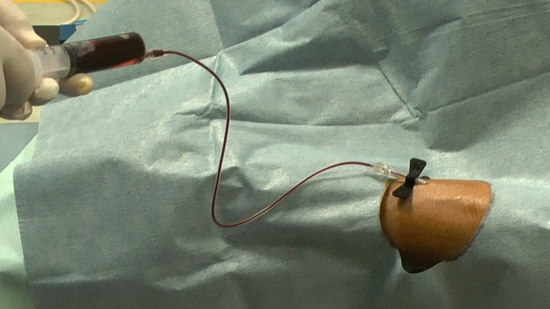

※ Differentiate an autologous blood syringe with a color needle

●Autologous blood syringe 20 cc - two

(1)Collect the blood of patients with autologous blood syringe

Because the contrast medium is administered beforehand, collect 16 cc blood twice

(5)Connect an extension tube to the puncture needle and fill the autologous blood syringe with the collected blood (mixture contrast medium).

(6)Infuse the autologous blood.

While communicating with the patient, observe the patient’s condition.

Check subjective physical condition of patients after 10 cc infusion and capture a projectional image.

Successively, inject all the autologous blood.